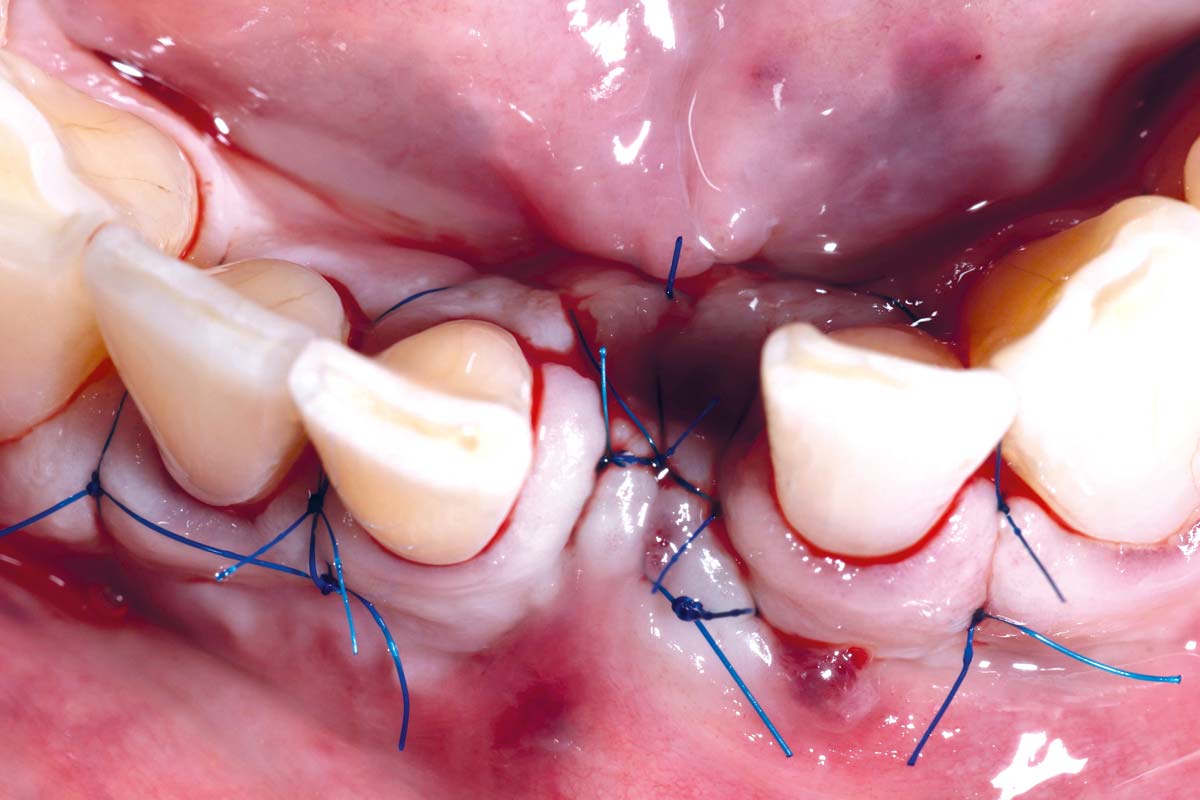

Immediately placed implant covered with permamem®. permamem® passively immobilized by sutures and intentionally left exposed to the oral cavity.